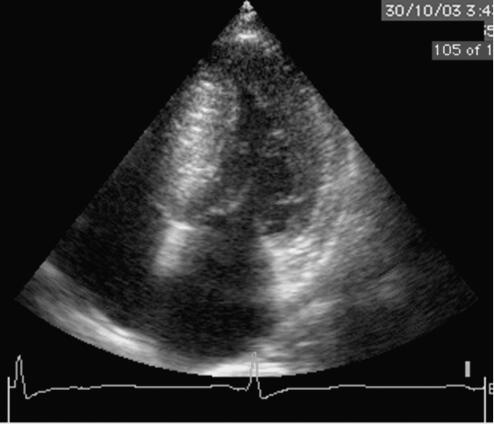

5﹒心动超声

左房内径40mm,左室舒张末内径45mm,室间隔厚21mm,左室后壁9mm,室间隔非对称性肥厚,与后壁之比>1.5;M型可见二尖瓣前叶在收缩期前移(SA M征+)。多普勒超声示左室流出道流速3.2m/s,二尖瓣少量反流,二尖瓣舒张期血流A峰>E峰。

(见图31‐22、图31‐23)

图31‐22 超声心动图表现(胸骨旁左心室长轴)

图31‐23 超声心动图表现(心尖4腔图)

3﹒超声心动图示左房扩大,室间隔不对称性肥厚,室间隔的厚度与左室后壁之比>1.5,左室流出道流速加快,SA M征+,左室顺应性减低;